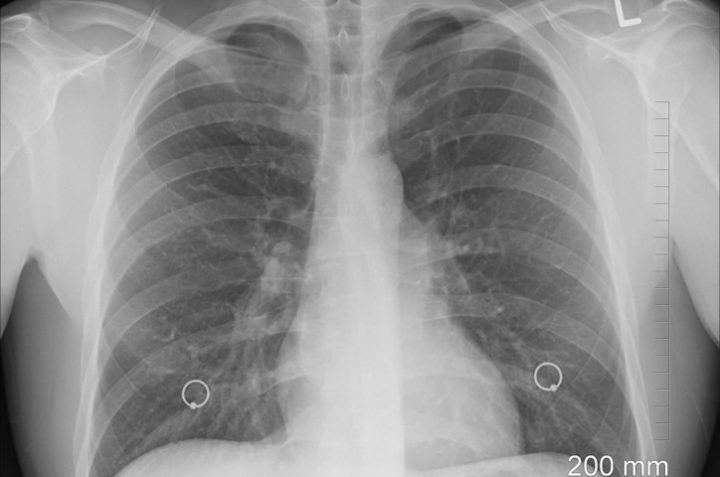

What Does Pneumonia Look Like? The signs and symptoms of pneumonia vary from mild to severe depending on your age, your health, and the type of germ that is causing the infection. Mild symptoms and signs are often similar to a cold or flu, but may last longer. Newborns...

Pneumonia is a serious health problem that is an infection or inflammation in the lungs. It can involve one lung or affect both lungs. Pneumonia can result from breathing in droplets of infective agents or germs from an infected person’s sneeze or cough, particularly in a closed space such...